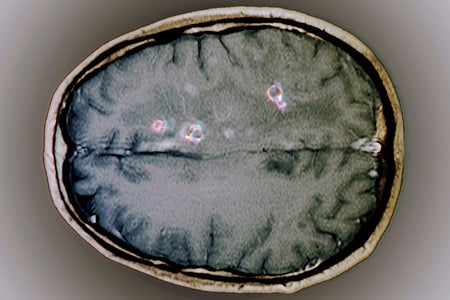

Brain Worms like the One in RFK, Jr.’s Head Are Actually a Global Problem

Experts explain how certain worms can infect the brain and why they are an important global public health problem